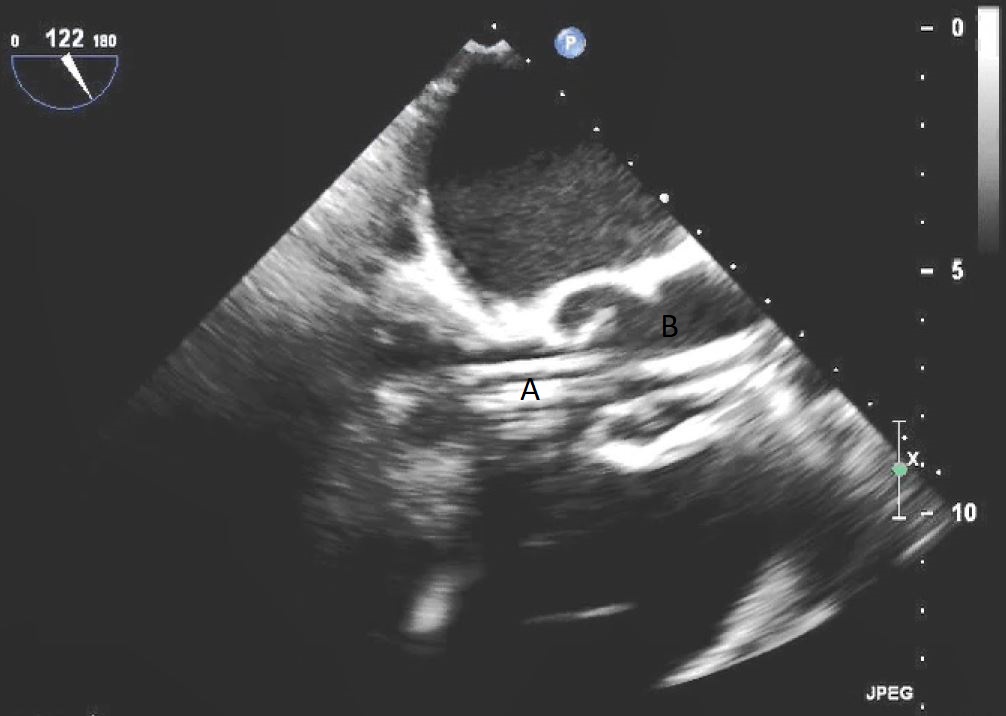

When examining the inflow cannula of the LVAD, the inflow cannula should be orientated and aligned with the mitral valve [47] (Figs. 19,20). Laminar flow from the ventricle to the device suggests a correctly aligned inflow cannula [56]. Obstruction of the inflow cannula manifests with increased turbulence and elevated doppler velocities [47].

Fig. 20.Transesophageal echocardiogram four chamber image with the LVAD inflow cannula pointing towards the septum (A). (B) LV (C) LA.